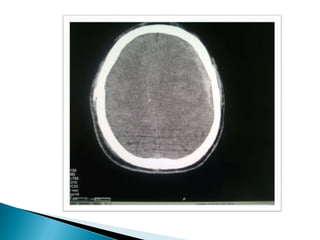

TAC Agudo 1-3 dias Hiperdenso Subagudo 4º dia- 3 semanas Isodenso Crónico > 3 semanas Hipodenso

Masa en forma de semiluna hiperdensa.  +/- Lesiones intraparenquimatosas.  Desplazamiento de línea media.  Edema cerebral.  Obliteración de cisternas basales.  Signos de herniación (subfacial, uncus...)  Obliteración de astas ventriculares ipsilaterales y dilatación de las contralaterales.